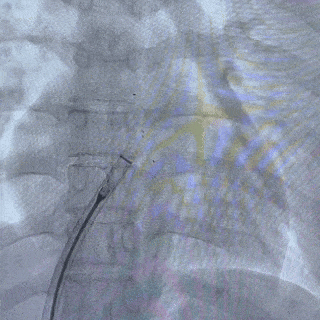

释放后影像

最后封堵器盘面稳固扣合,形态扁平且位置良好,封堵成功

手术过程采用DSA+经胸超声引导,封堵后,超声下显示盘面稳固扣合,形态扁平且位置良好,夹闭膨出瘤,未见残余分流,未见心包积液,封堵前后均无不良反应,封堵成功。